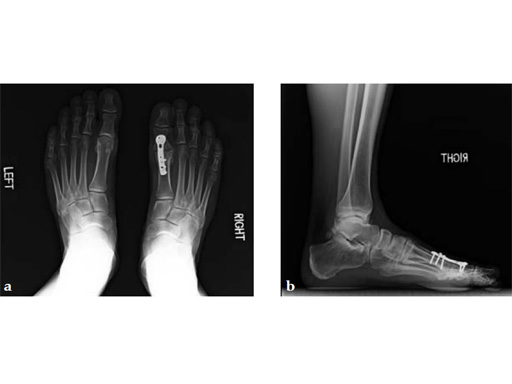

Case 3: First TMT fusion plate

A 48-year-old woman, with hallus valgus and hypermobile medial column, also resulting in pes plano abductovalgus (flatfoot).

Case provided by Andrew Sands, New York, New York, USA

Surgery consisted of first TMT and intertarsal corrective osteotomy plus fusion with movement of the first MT lateral and plantar. This corrects the hallus valgus as well as the PPAV (and stabilizes the medial column).